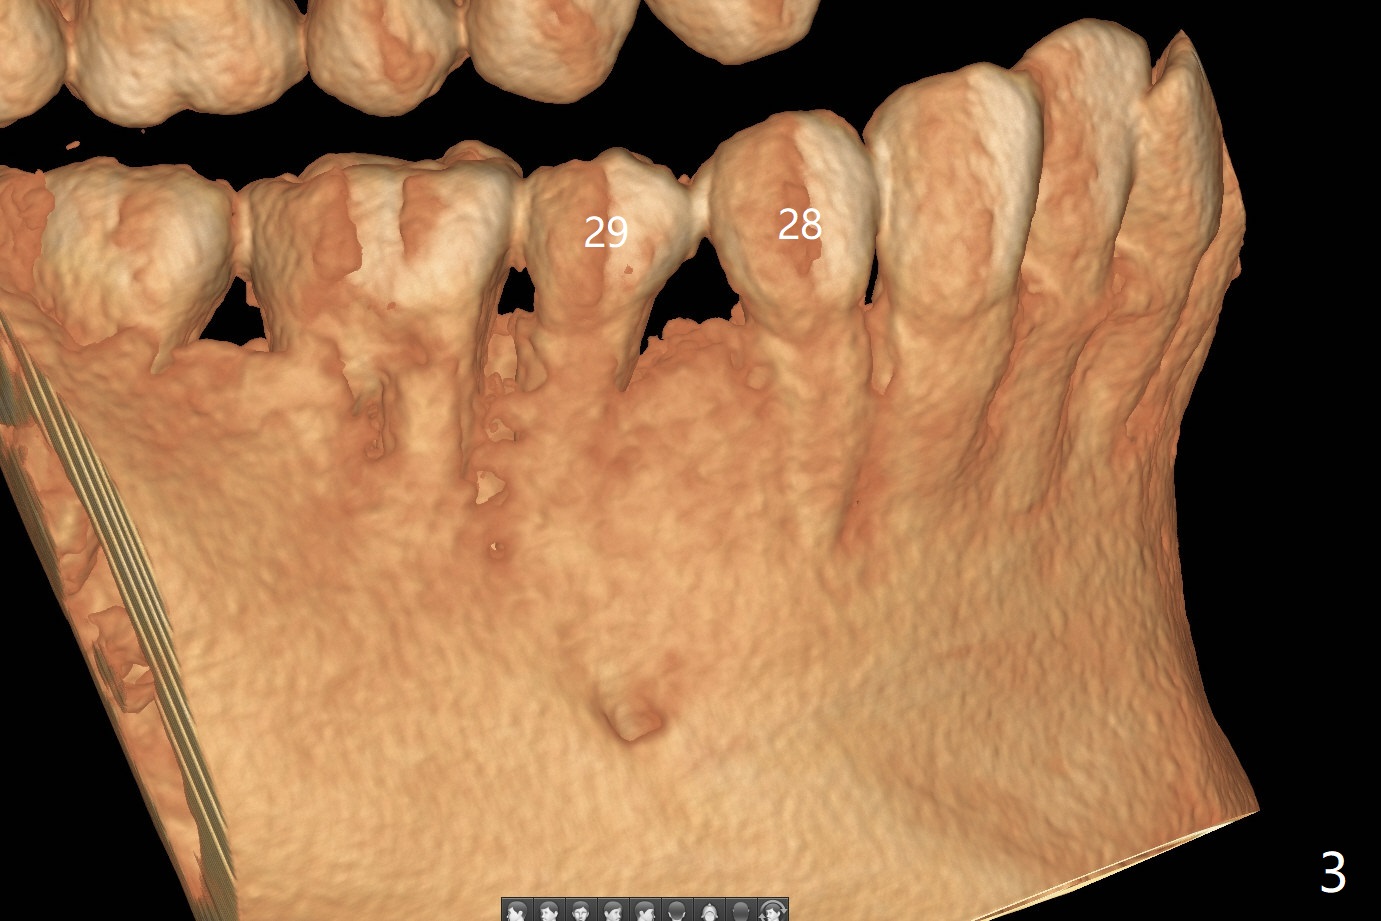

CT is taken 4 months post panoramic X-ray (Fig.2).  C: coronal; S: sagittal; A: axial; B: buccal.  Coronal (Fig.6) and sagittal (Fig.7) sections.  It seems that the lesion does not invade the thin buccal plate or the periodontium.